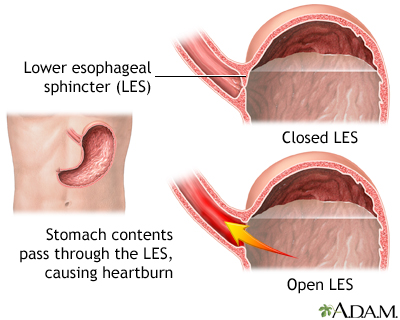

Normally when food or liquid enters your stomach, a band of muscle at the lower end of your esophagus closes off the esophagus. This band is called the lower esophageal sphincter (LES). If this band does not close tightly enough, food or stomach acid can back up (reflux) into the esophagus. The stomach contents can irritate the esophagus and cause heartburn and other symptoms.